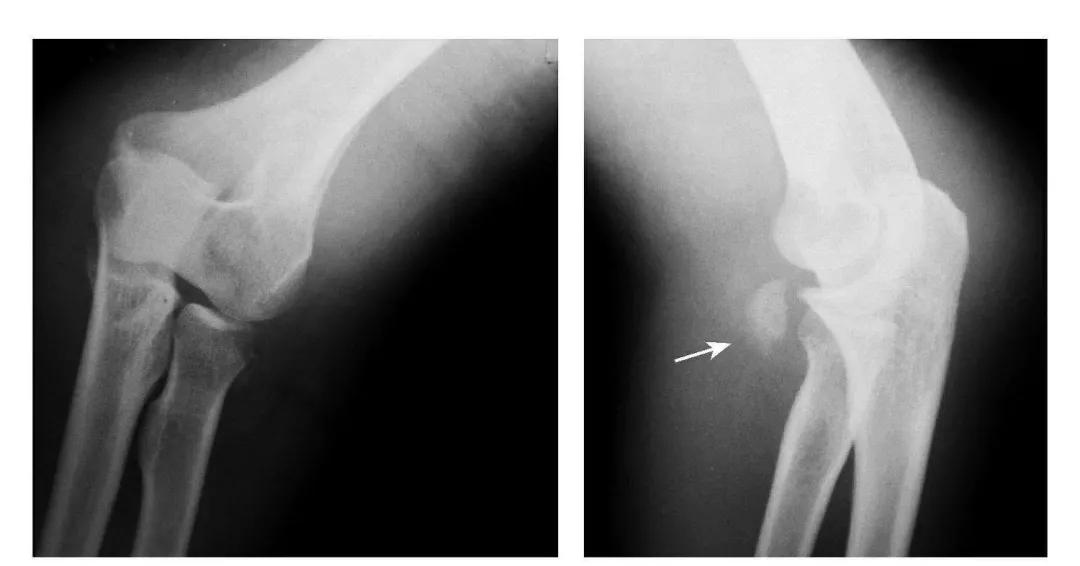

肱骨下端双髁骨折

例1:肱骨内髁及外髁骨折,该两髁骨块均呈向内、外翻转移位。

例2:肱骨内上髁Ⅲ度骨折并外上髁撕脱骨折。

例3:肱骨内上髁Ⅳ度骨折并外上髁撕脱骨折。